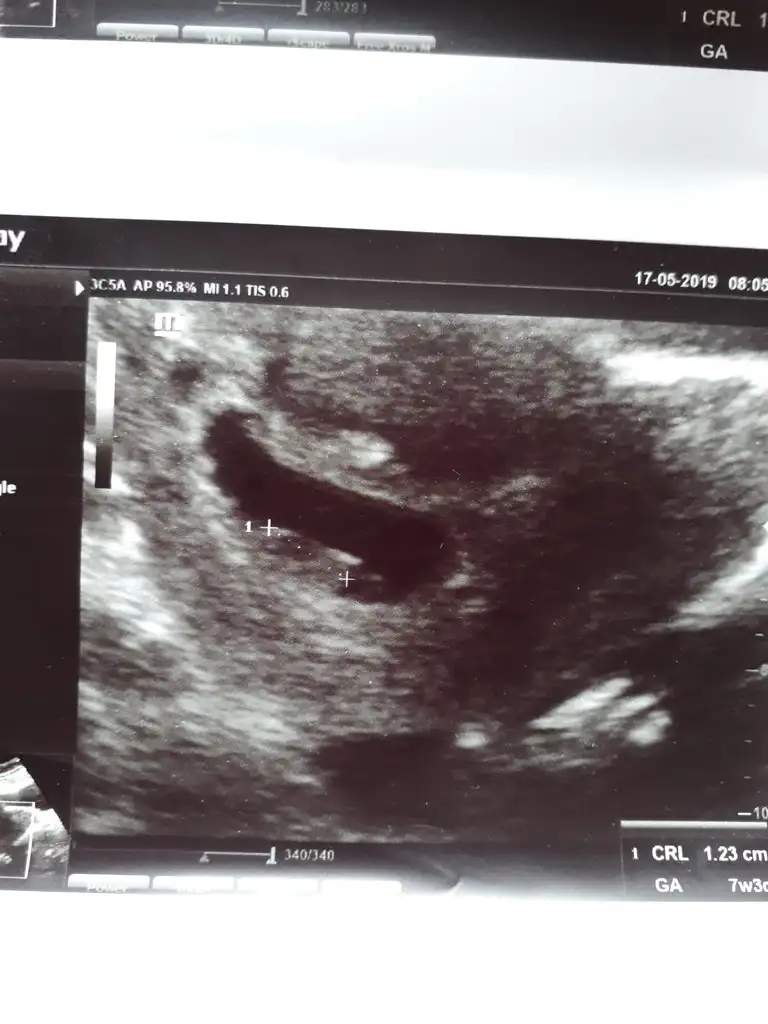

7+4 karından ultrason bana da bir yorum yapar mısınız?

Canım seninki karından ultrason sa solda erkek oluyor bu teori şuan etrafımdaki hamilelerde tuttu arkdaşımın sağdaydı kızı olacağını öğrendi dün bir tanıdıgımızın da soldaydı onada doktor yüzde yüz oğlan demiş ablamında oğlu olacak onun ultrason fotograflarına baktık onunki de soldaCanim banada yorum yaparmisin karindan usg

Hadi bakaljm Insallah yorumun icin cok tesekkur ederim canim ❤Canım seninki karından ultrason sa solda erkek oluyor bu teori şuan etrafımdaki hamilelerde tuttu arkdaşımın sağdaydı kızı olacağını öğrendi dün bir tanıdıgımızın da soldaydı onada doktor yüzde yüz oğlan demiş ablamında oğlu olacak onun ultrason fotograflarına baktık onunki de soldateori tutuyor yani bakalım görcz